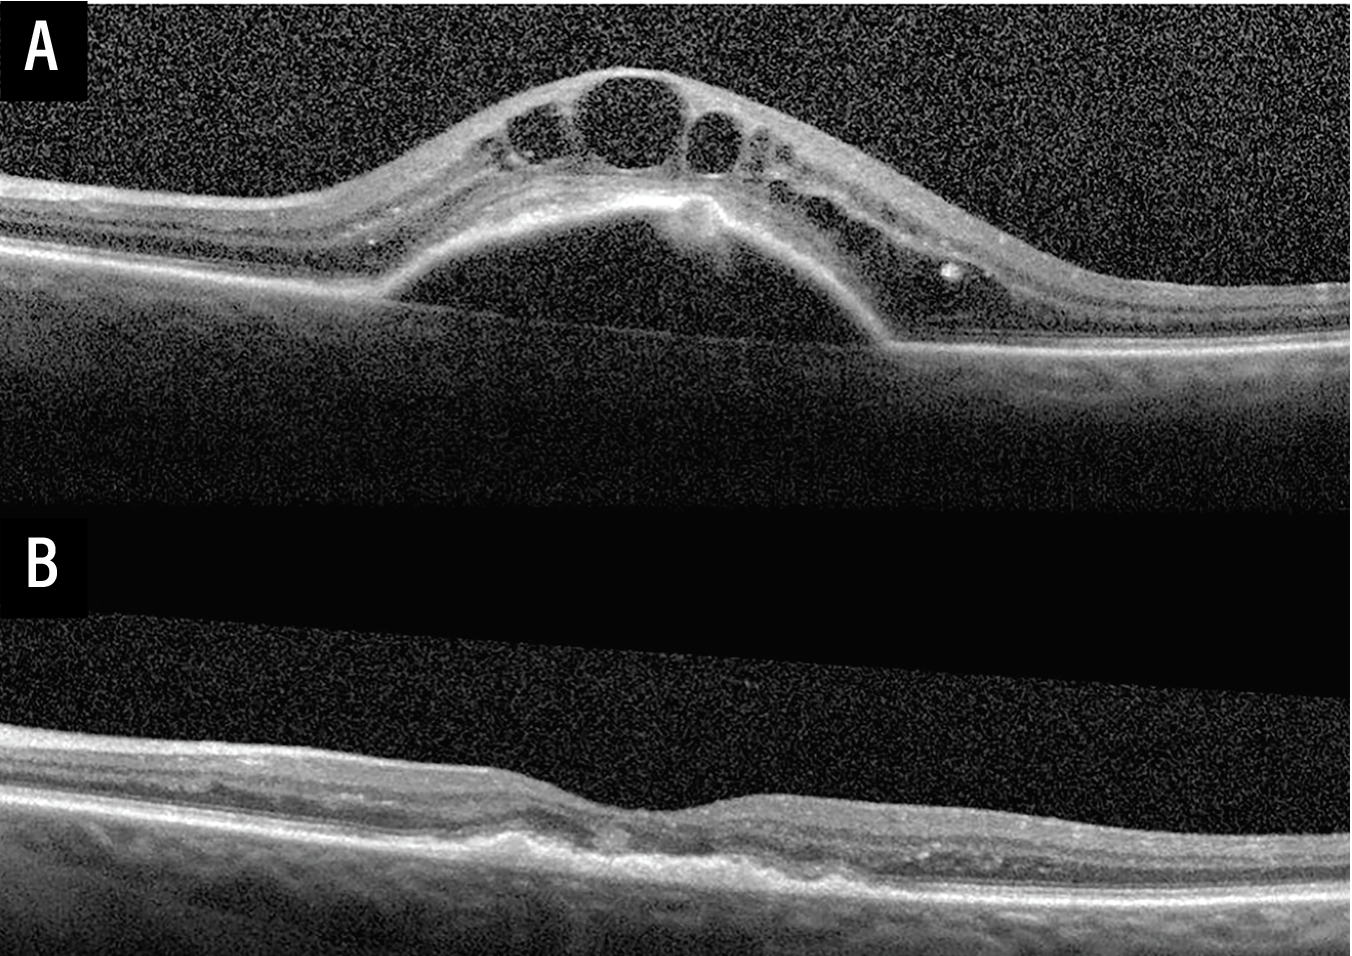

| Figure 1. Optical coherence tomography images demonstrating treatment response to intravitreal anti-VEGF therapy in treatment naive neovascular age-related macular degeneration. (A) Baseline OCT of the left eye at the time of presentation with neovascular AMD demonstrating a fibrovascular pigment epithelial detachment, subretinal hyperreflective material (SRHM), and intraretinal fluid. (B) Follow-up OCT of the same eye following three monthly loading intravitreal anti-VEGF injections demonstrating marked reduction in PED height and complete resolution of IRF—illustrating the robust anatomic response that supports a treat-until-dry management approach. |